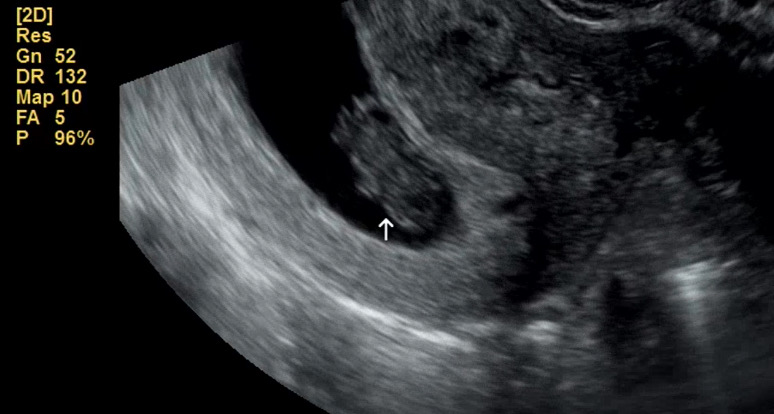

거꾸로 콩 박혀있는 울 쩰리곰 8주 6일 됐어요 심박동수 179회 🫶 일하느라 맨날 뛰어다니고 여기저기 부딪히고 화내고 다하는데 건강히 붙어있어줘서 너무 고마워